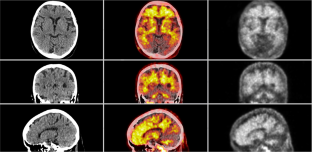

Fig. 1